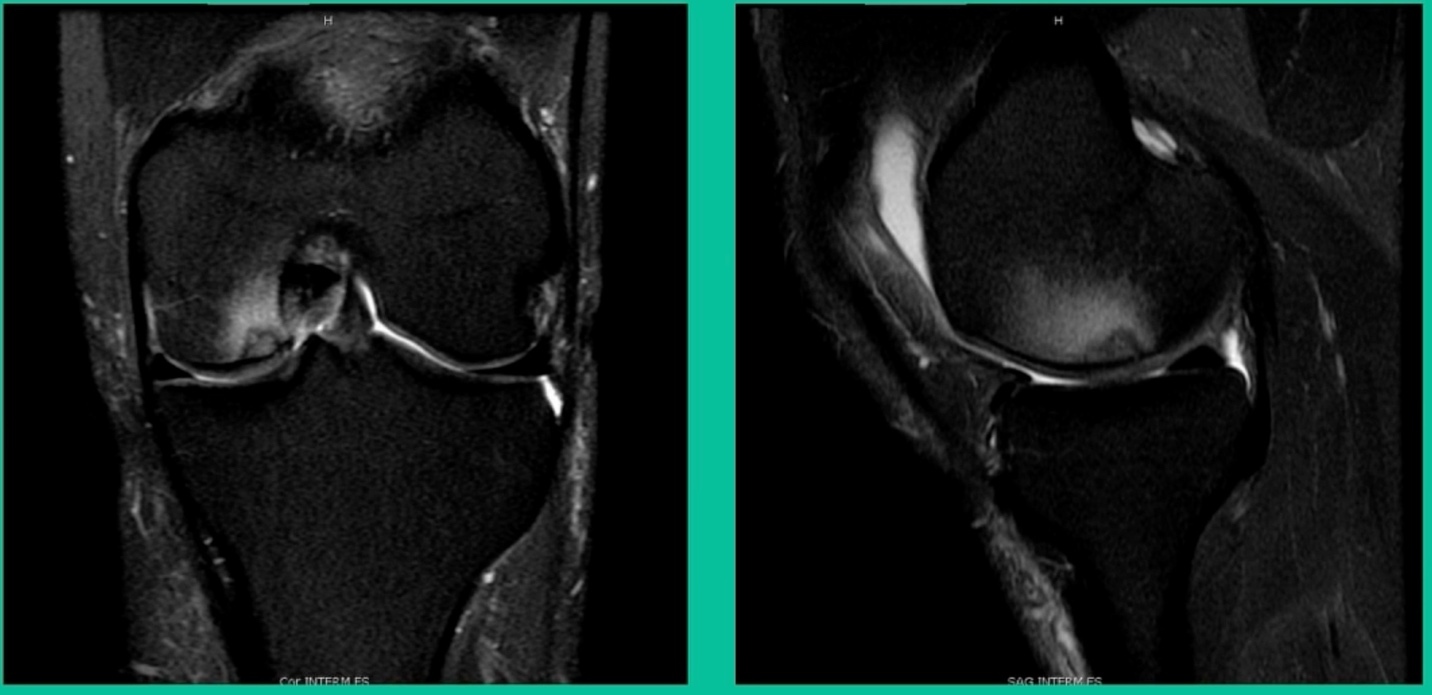

43-Year-Old, symptomatic medial femoral condyle.

D1 football player formally, affecting ADLs. For this one, I initially just wanted to watch it. This looks pretty small when he came in. Let’s see what happens. Six months later, this is where he progressed to.

We get in there, it’s delaminated, not much bone, nothing to fix in my mind, and so we drilled it.

How do these do? There’s actually reasonable data for marrow stimulation for OCD. But if you have the option for small defects, I would prefer an osteochondral allograft over microfracture based on the literature. That’s the take-home. Marrow stimulation, if you do it, you’re probably better off drilling it. We showed that we could reduce revision rates with marrow stimulation by two-thirds if you drill it versus use a microfracture awl.

This is an 18-year-old with a lateral femoral condyle OCD:

Worsening over the last two years, has effusions but no locking, and has a large area of involvement that appears unstable. This is the classic fixation. If you can do this, this is the holy grail. Remember, fracture non-union: you elevate it, debride the base, get rid of any unstable fragments, just take them out, and preserve the major fragment. I’ll use a microfracture awl, but most commonly now I’ll use a pick or a pin, and I’ll drill it. I use two to three metal screws. I bury their heads, and then I come back at eight weeks after being non-weight-bearing, and pull the screws out.

Afterwards, I’ll allow them to fully weight-bear, wait eight more weeks, and then they go back to full sports. How do these do? Amazing. If you can get this to heal in an adult, this should last hopefully forever. The results over here show 80 to 90 percent healing rates in most series.